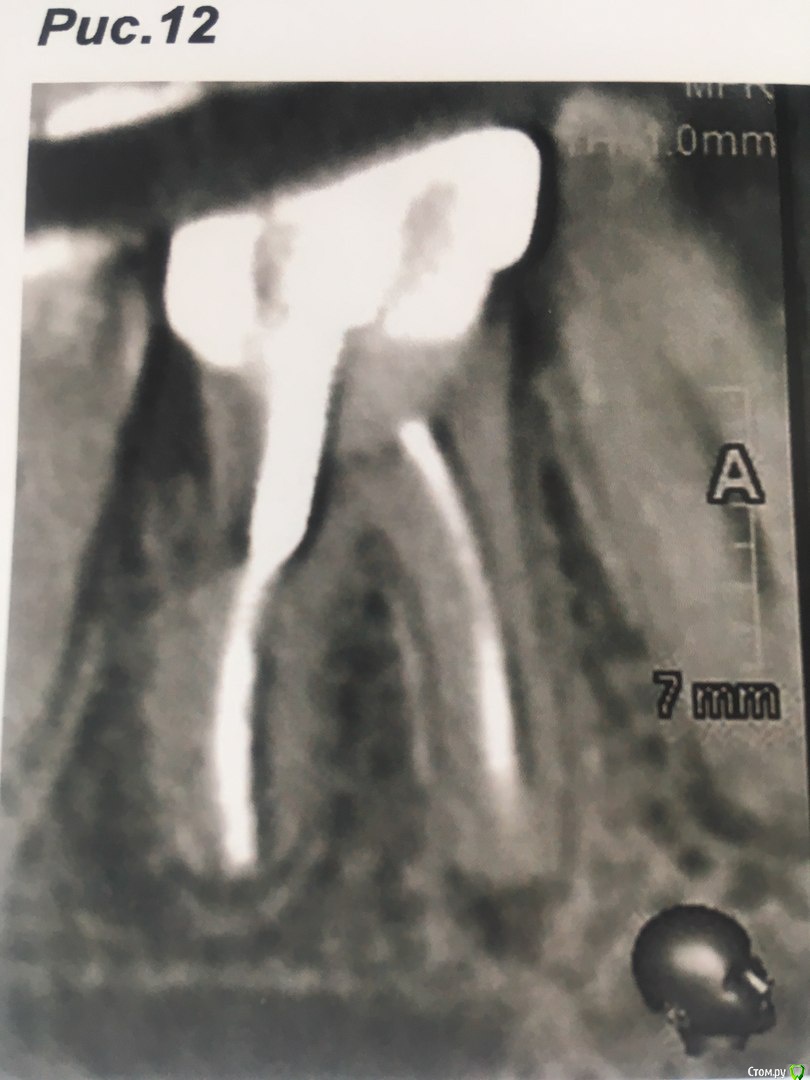

Коронковой части у зуба практически нет,только корень, поставлен штиф  и на него пломба в виде коронки зуба.

В течении  года от зуба опустилась десна и там проглядывается прозрачно-черный корень и очень быстро на 5 и 4-ки обазовались черные пятна.  Сделала КТ. Теперь стоит вопрос долгое  лечение или удаление.Врач говорит все будет видно при вскрытии. Если лечение то долгое и без гарантий.   Мне кажется от корня там мало что осталось,судя по цвету и по тому как быстро испортились рядом стоящие зубы. Может проще не лечить,установить имплант?

Правда один врач сказал,что то вроде убыли костной ткани и имплант удержать будет не чем,кроме того сужение верхней челюсти, рецессия десны и стирание в пришеечной области из за прикуса. В заключении кт -пародонтопатия легкой степени тяжести.

соглашусь, решение нужно принимать после оценки объема оставшихся твердых тканей и перспективы протезирования. Если судить только по снимкам, то скорее удалять...